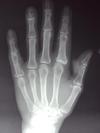

Diagnosis?

Imaging findings?

Psoriatic arthritis. Hands and feet most commonly involved. Rheumatoid factor negative, 60% HLA-B27 positive. Skin findings precede arthritis in 90%.

Periarticular marginal erosions and proliferation of bone (leads to “fuzzy” appearance). May see: pencil in cup deformity, sausage digit, “ivory phalynx-“

sclerotic distal phalanx of great toe, late- arthritis mutilans, asymmetrical sacroiliitis.